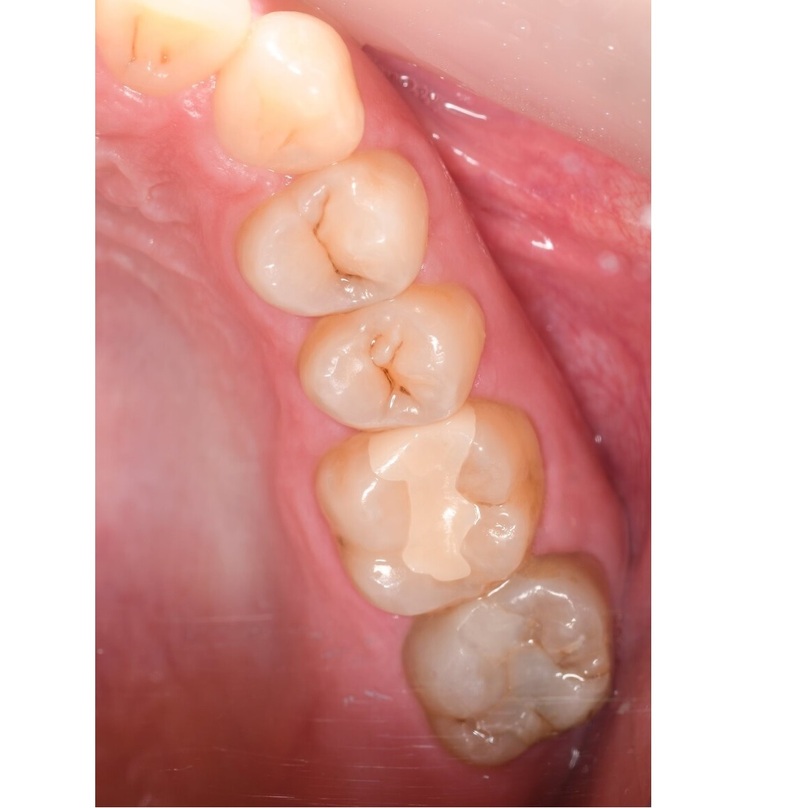

奥歯のジルコニア

の症例

| 年齢・性別 | 22歳・男性 |

| 主訴・治療部位 | 他院で虫歯治療 詰め物の治療が必要と判断を受けたが、自費診療の費用が高価で治療を断念 インターネットで当院を知りご来院 右上6番、右上4番 |

| 治療費用 | 合計:88,000円 ジルコニア:44,000円×2 (2023年1月現在) |

| 治療期間 | 約1ヵ月 |

| 治療内容 | 虫歯を除去し、型をとりました。 神経の近くまで虫歯になっていたため、神経の保護処置も行いました。 |

| リスク・副作用 | 虫歯が進行し、神経の治療になる可能性があります。 神経の近くまで削っているため、治療直後は敏感になり痛みが出る可能性があります。 かみ合わせの強い方は詰め物が取れてしまう可能性があります。 |

| 治療方針 | 治療必要な箇所は終了 親知らずは埋まっているが、痛みや腫れはないため、定期検診にて経過観察していきます。 |

| 担当者所見 | 歯周病検査は異常なし 虫歯リスクを下げるため、歯ブラシの他にフロスや歯間ブラシの併用を提案しました。 |